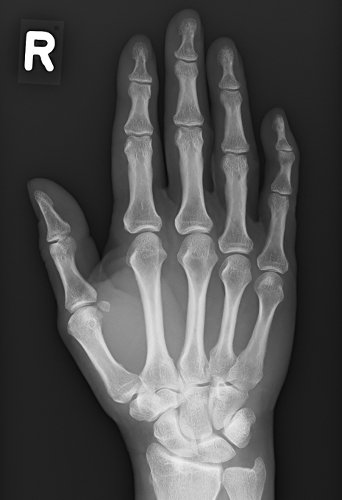

Behandlungsbeispiel

Die Orthovolttherapie ist eine schmerzfreie, nichtinvasive Behandlung mit speziellen energetischen Röntgenstrahlen.

Sie vereinabren telefonisch oder persönlich einen Termin mit uns und bringen zur Erstvorstelldung bitte Ihre Versichertenkarte und Überweisung und, falls vorhanden, auch Röntgenbilder der zu bestrahlenden Körperregion mit.